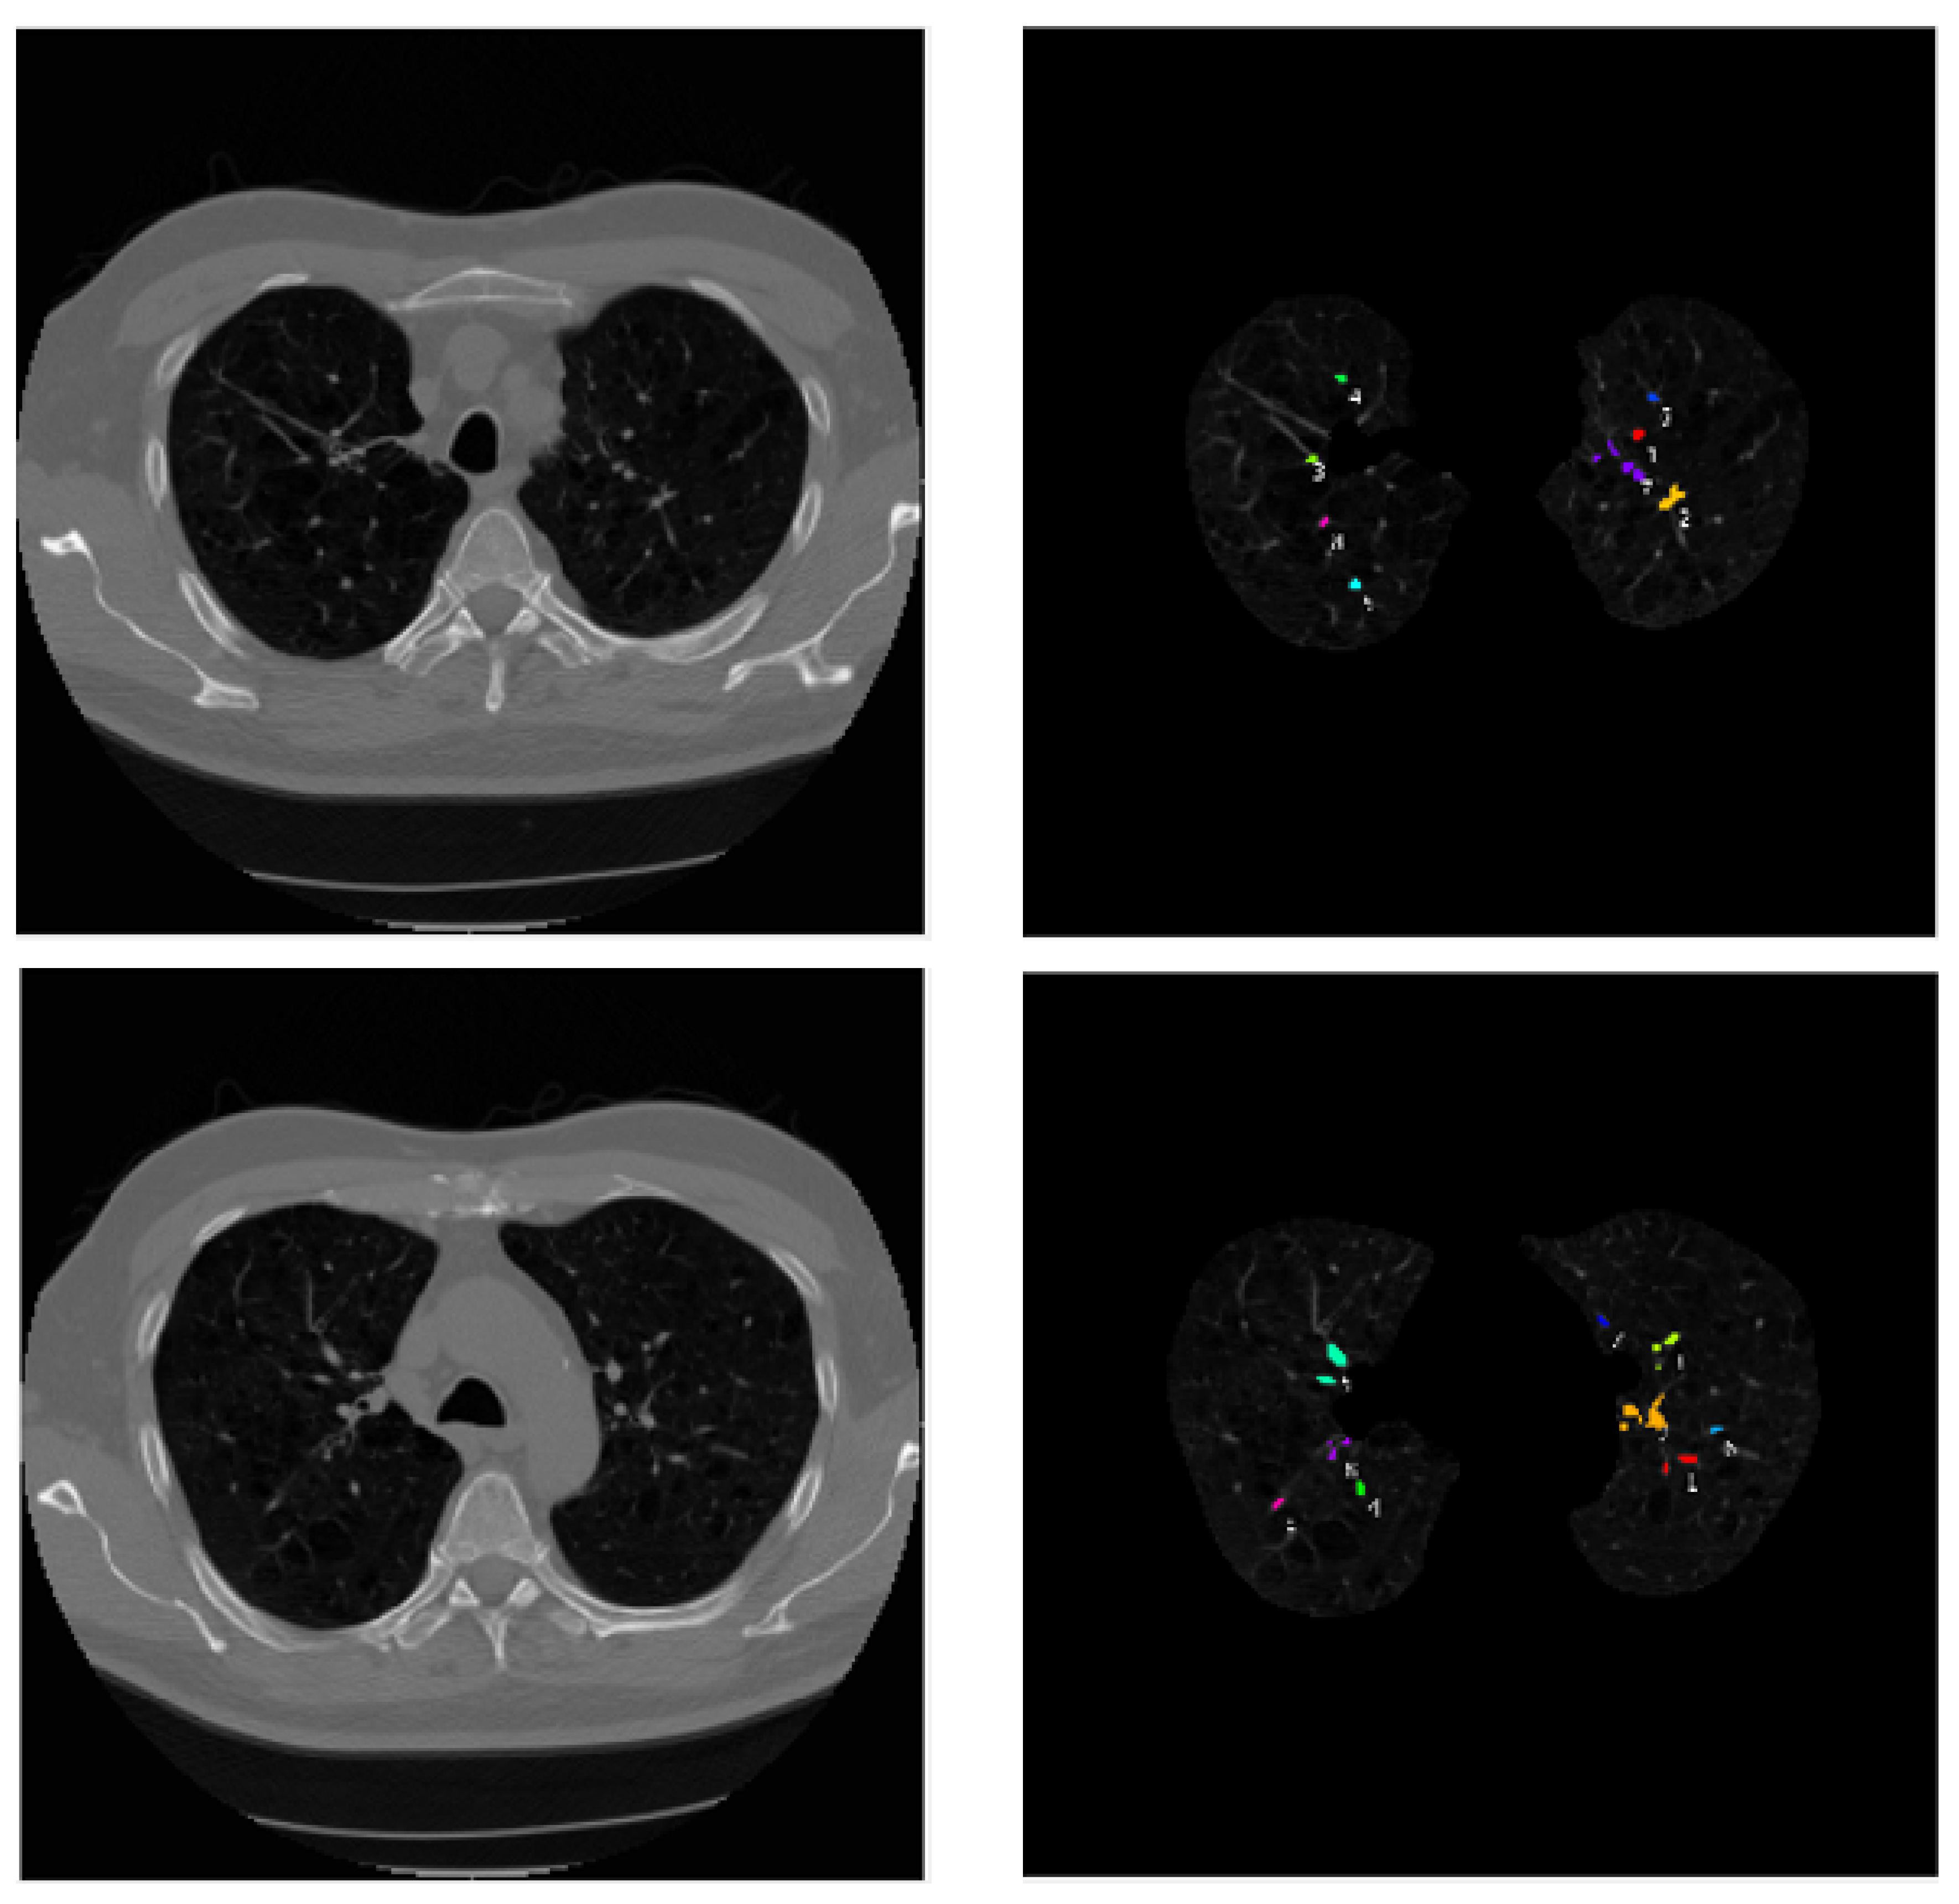

4. Experiments and Simulations